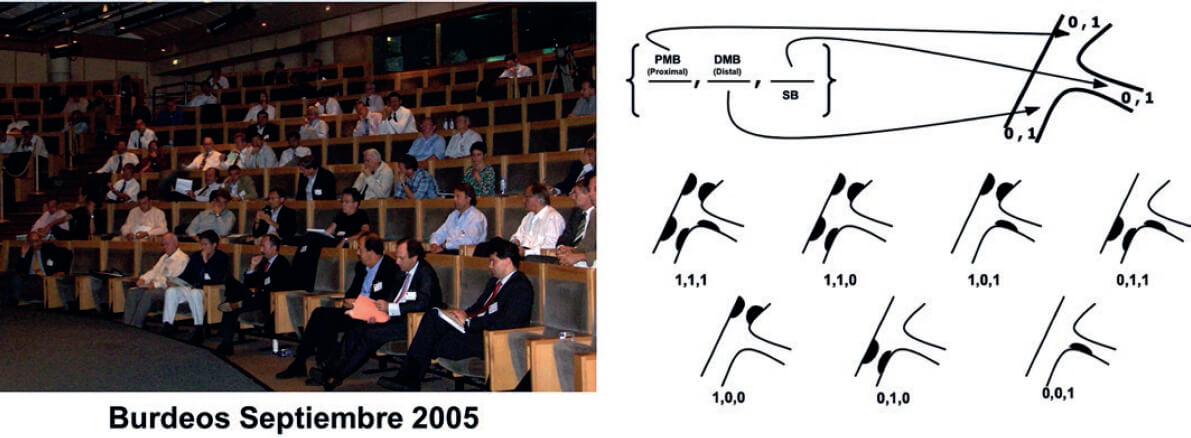

Se han propuesto varias clasificaciones para definir las características basales de las bifurcaciones, algunas durante de la era de los stents metálicos. Sin embargo, la más aceptada actualmente es la clasificación de Medina6 (figura 2). Su éxito se debe a su sencillez y a lo fácil que resulta memorizarla. Esta clasificación fue aceptada en septiembre de 2005 en la primera reunión del European Bifurcation Club, en Burdeos (figura 2), donde los autores de la clasificación de Massy renunciaron a su propia clasificación para adoptar la nueva6 como la única propuesta por este grupo. Tras captar la importancia de tal hecho, la clasificación se publicó en Revista Española de Cardiología y alcanzó un récord de citaciones (el artículo más citado de toda su historia).

Figura 2. A la izquierda: reunión de Burdeos en septiembre de 2005, en la que se propuso la clasificación de Medina como la única aceptada por el European Bifurcation Club. A la derecha: clasificación de Medina, reproducida con permiso de Medina et al.6. DMB: distal main branch (vaso principal distal); PMB: proximal main branch (vaso principal proximal); SB: side branch (rama lateral).